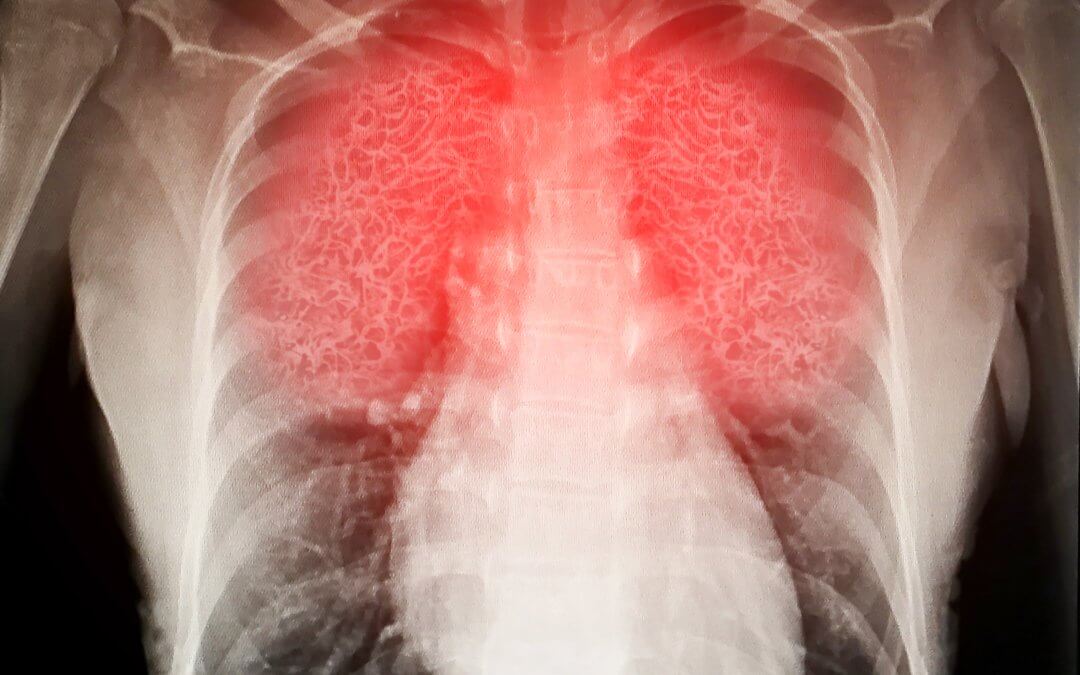

When a severe illness, infection, or injury affects the lungs, inflammation can cause fluid to accumulate, leading to Acute Respiratory Distress Syndrome (ARDS).[1][2] With limited effective treatments, this life-threatening condition remains a major medical challenge. Stem cell therapies are being investigated as a potential supportive treatment; recent reviews summarise current findings and identify areas for further research.[3][4]

Normally, small sacs in the lungs called alveoli fill with air during breathing. Oxygen passes from the alveoli into the blood, while carbon dioxide moves from the blood into the alveoli to be exhaled.[5]

In ARDS, inflammation can damage the alveolar membrane, allowing fluid to leak into the alveoli. This reduces oxygen transfer to the blood, which can impair organ function.[1][2] ARDS often develops within hours to days of the illness or injury that triggered it and can worsen rapidly. Complications may include multiple organ failure and cognitive issues due to low oxygen levels.[1][2][6] Mortality in ARDS varies according to severity, with clinical data suggesting rates of approximately 27% in mild cases and up to around 45% in more severe disease.[7] Survivors may experience long-term impacts, including reduced lung function and other consequences related to prolonged hospitalisation and mechanical ventilation.[6]